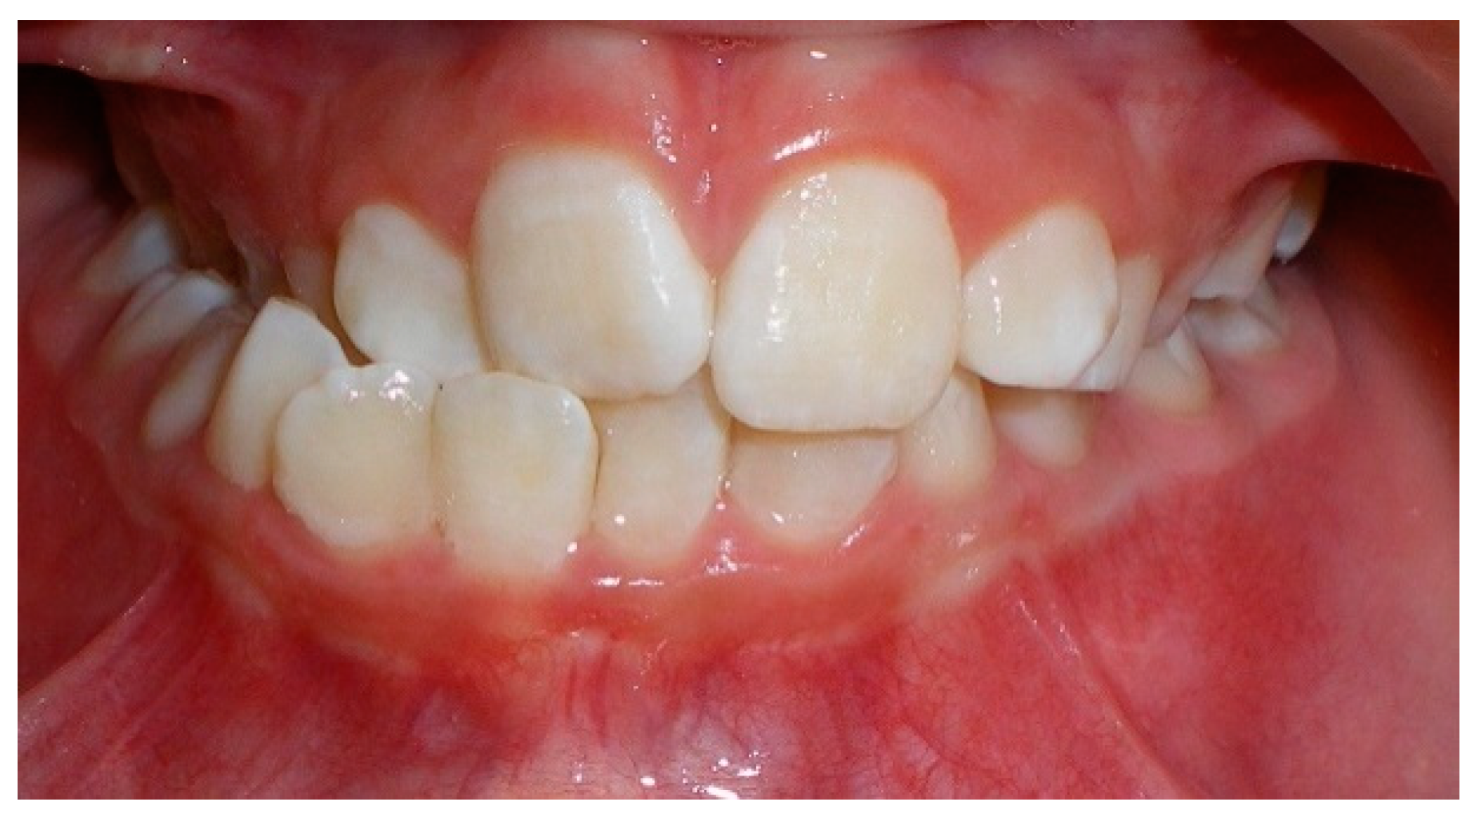

- Evaluation of buccal and lingual cortical plates: Figure 5, Figure 6 and Figure 7 show a case in which the mandibular lateral incisors are positioned lingual to the central incisors. Both mandibular lateral incisors are adjacent to each other. Figure 5 shows and intraoral occlusal photos with retained deciduous mandibular lateral incisors. There was no way to evaluate the buccal and lingual cortical plates through conventional 2D panoramic, periapical or occlusal radiographs. Therefore, CBCT was acquired and collimated to the area of teeth in order to assess the relationship of the four mandibular incisors to the labial and lingual cortical plates as well as to the adjacent teeth. As Figure 6 and Figure 7 display, CBCT shows that all permanent mandibular incisors are sound. It is important to note that thin buccal and lingual cortical plates may not be seen via CBCT—this does not denote that they are not present. In other words, CBCT images may not show a clinically present thin buccal and lingual cortical plates. In this case, the diagnostic information obtained from CBCT is far more significant than the information obtained from any other radiographic imaging technique.